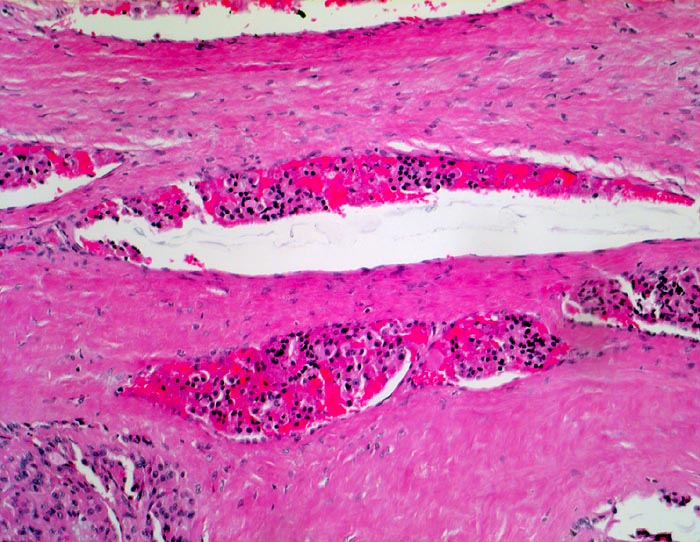

Follikuläres Schilddrüsenkarzinom: Gefässeinbruch

Mehrere Venen in der dicken Tumorkapsel enthalten

Tumorzellaggregate.

Vor einem Jahr Schilddrüsenteilresektion wegen follikulärem Karzinom. Jetzt Resthyreoidektomie wegen Rezidiv.

Histologie

100